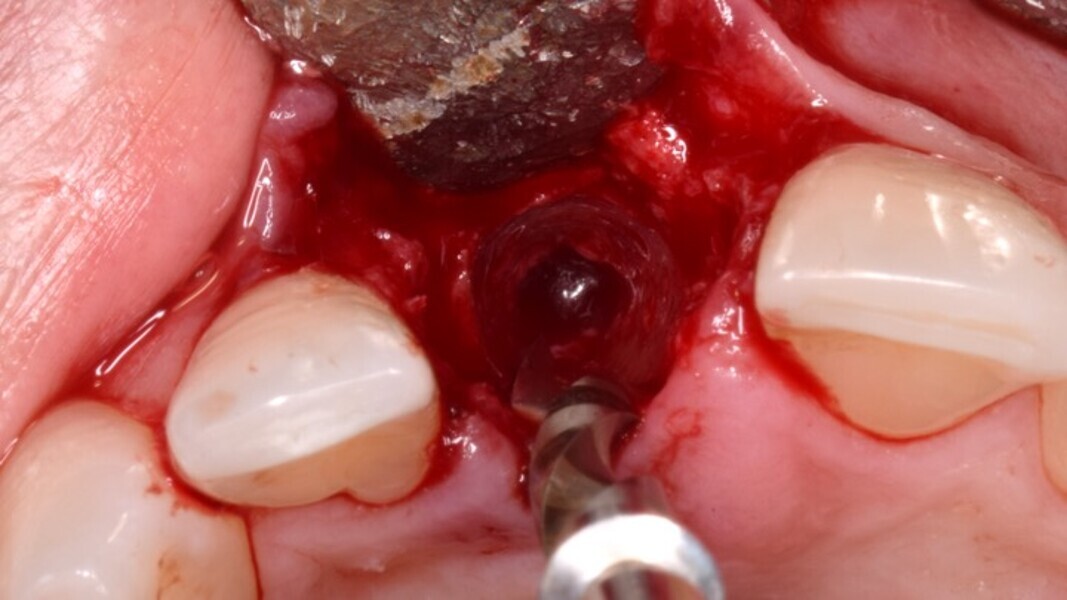

Figura 6. A pesar del defecto óseo, siempre buscamos la posibilidad de crear un nuevo alveolo quirúrgico que emerja por la zona del cíngulo de los dientes adyacentes, es decir, el margen de emergencia adecuado. En estos defectos, intentamos siempre el anclaje en profundidad con implantes largos de unos 16 mm debido al gran defecto existente. Es la única forma de que la estabilidad primaria del implante permita realizar una Prótesis Inmediata.

Figura 7. Implante de conexión interna insertado 2 mm por debajo de la cresta ósea, independientemente del defecto existente y a 55 Nw. Al no existir margen vestibular, tomamos como referencia los dos picos óseos de las papilas y entre ellos trazamos una línea imaginaria que los una enterrando el hombro unos 2 ó 3 mm por debajo de ella.